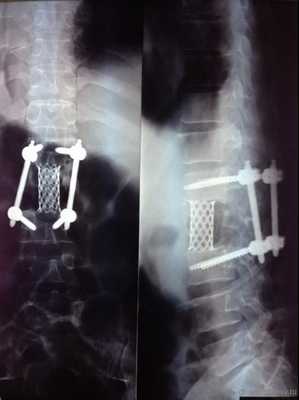

Фиксация на 360 градусов

Фиксация на 270 градусов — использование только с одной стороны 2-х винтов (там, где проводилось удаление фасет-сустава и устанавливался межтеловой кейдж (т.н. TLIF)